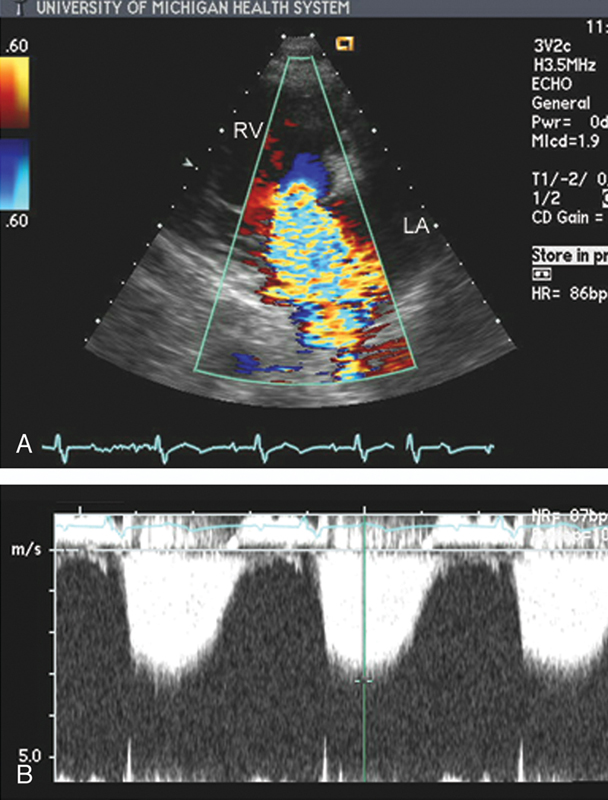

فحوصات تشخيصية لبعض امراض القلب والشرايين التاجية